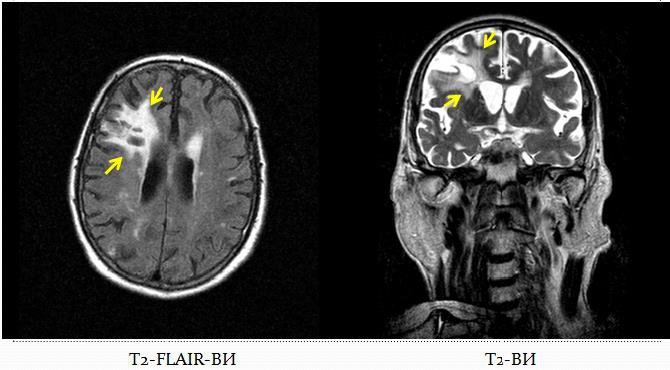

Кистозно-глиозная трансформация белого вещества головного мозга, как результат перенесенного ишемического нарушения мозгового кровообращения: